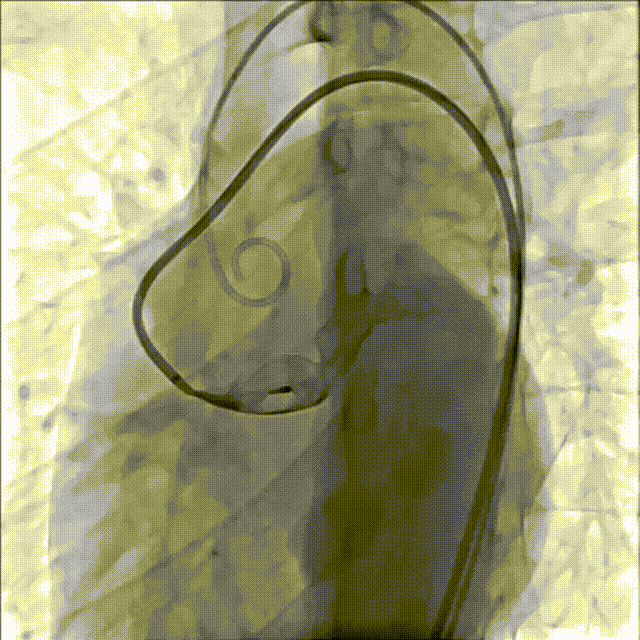

送入14mmAVP-II血管封堵器并定位释放

造影检查封堵位置及封堵效果